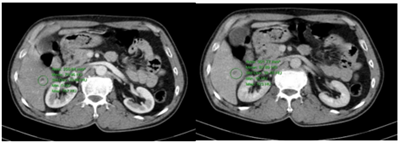

UNG THƯ BIỂU MÔ TẾ BÀO THẬN

Ung thư thận là loại ung thư thường gặp đứng thứ 14 trên toàn cầu, với hơn 430.000 ca mới được chẩn đoán vào năm 2020, và 434840 ca mắc trên toàn cầu vào năm 2022. Tỷ lệ mắc thay đổi theo khu vực địa lý, cao hơn ở châu Âu và Bắc Mỹ. Ung...